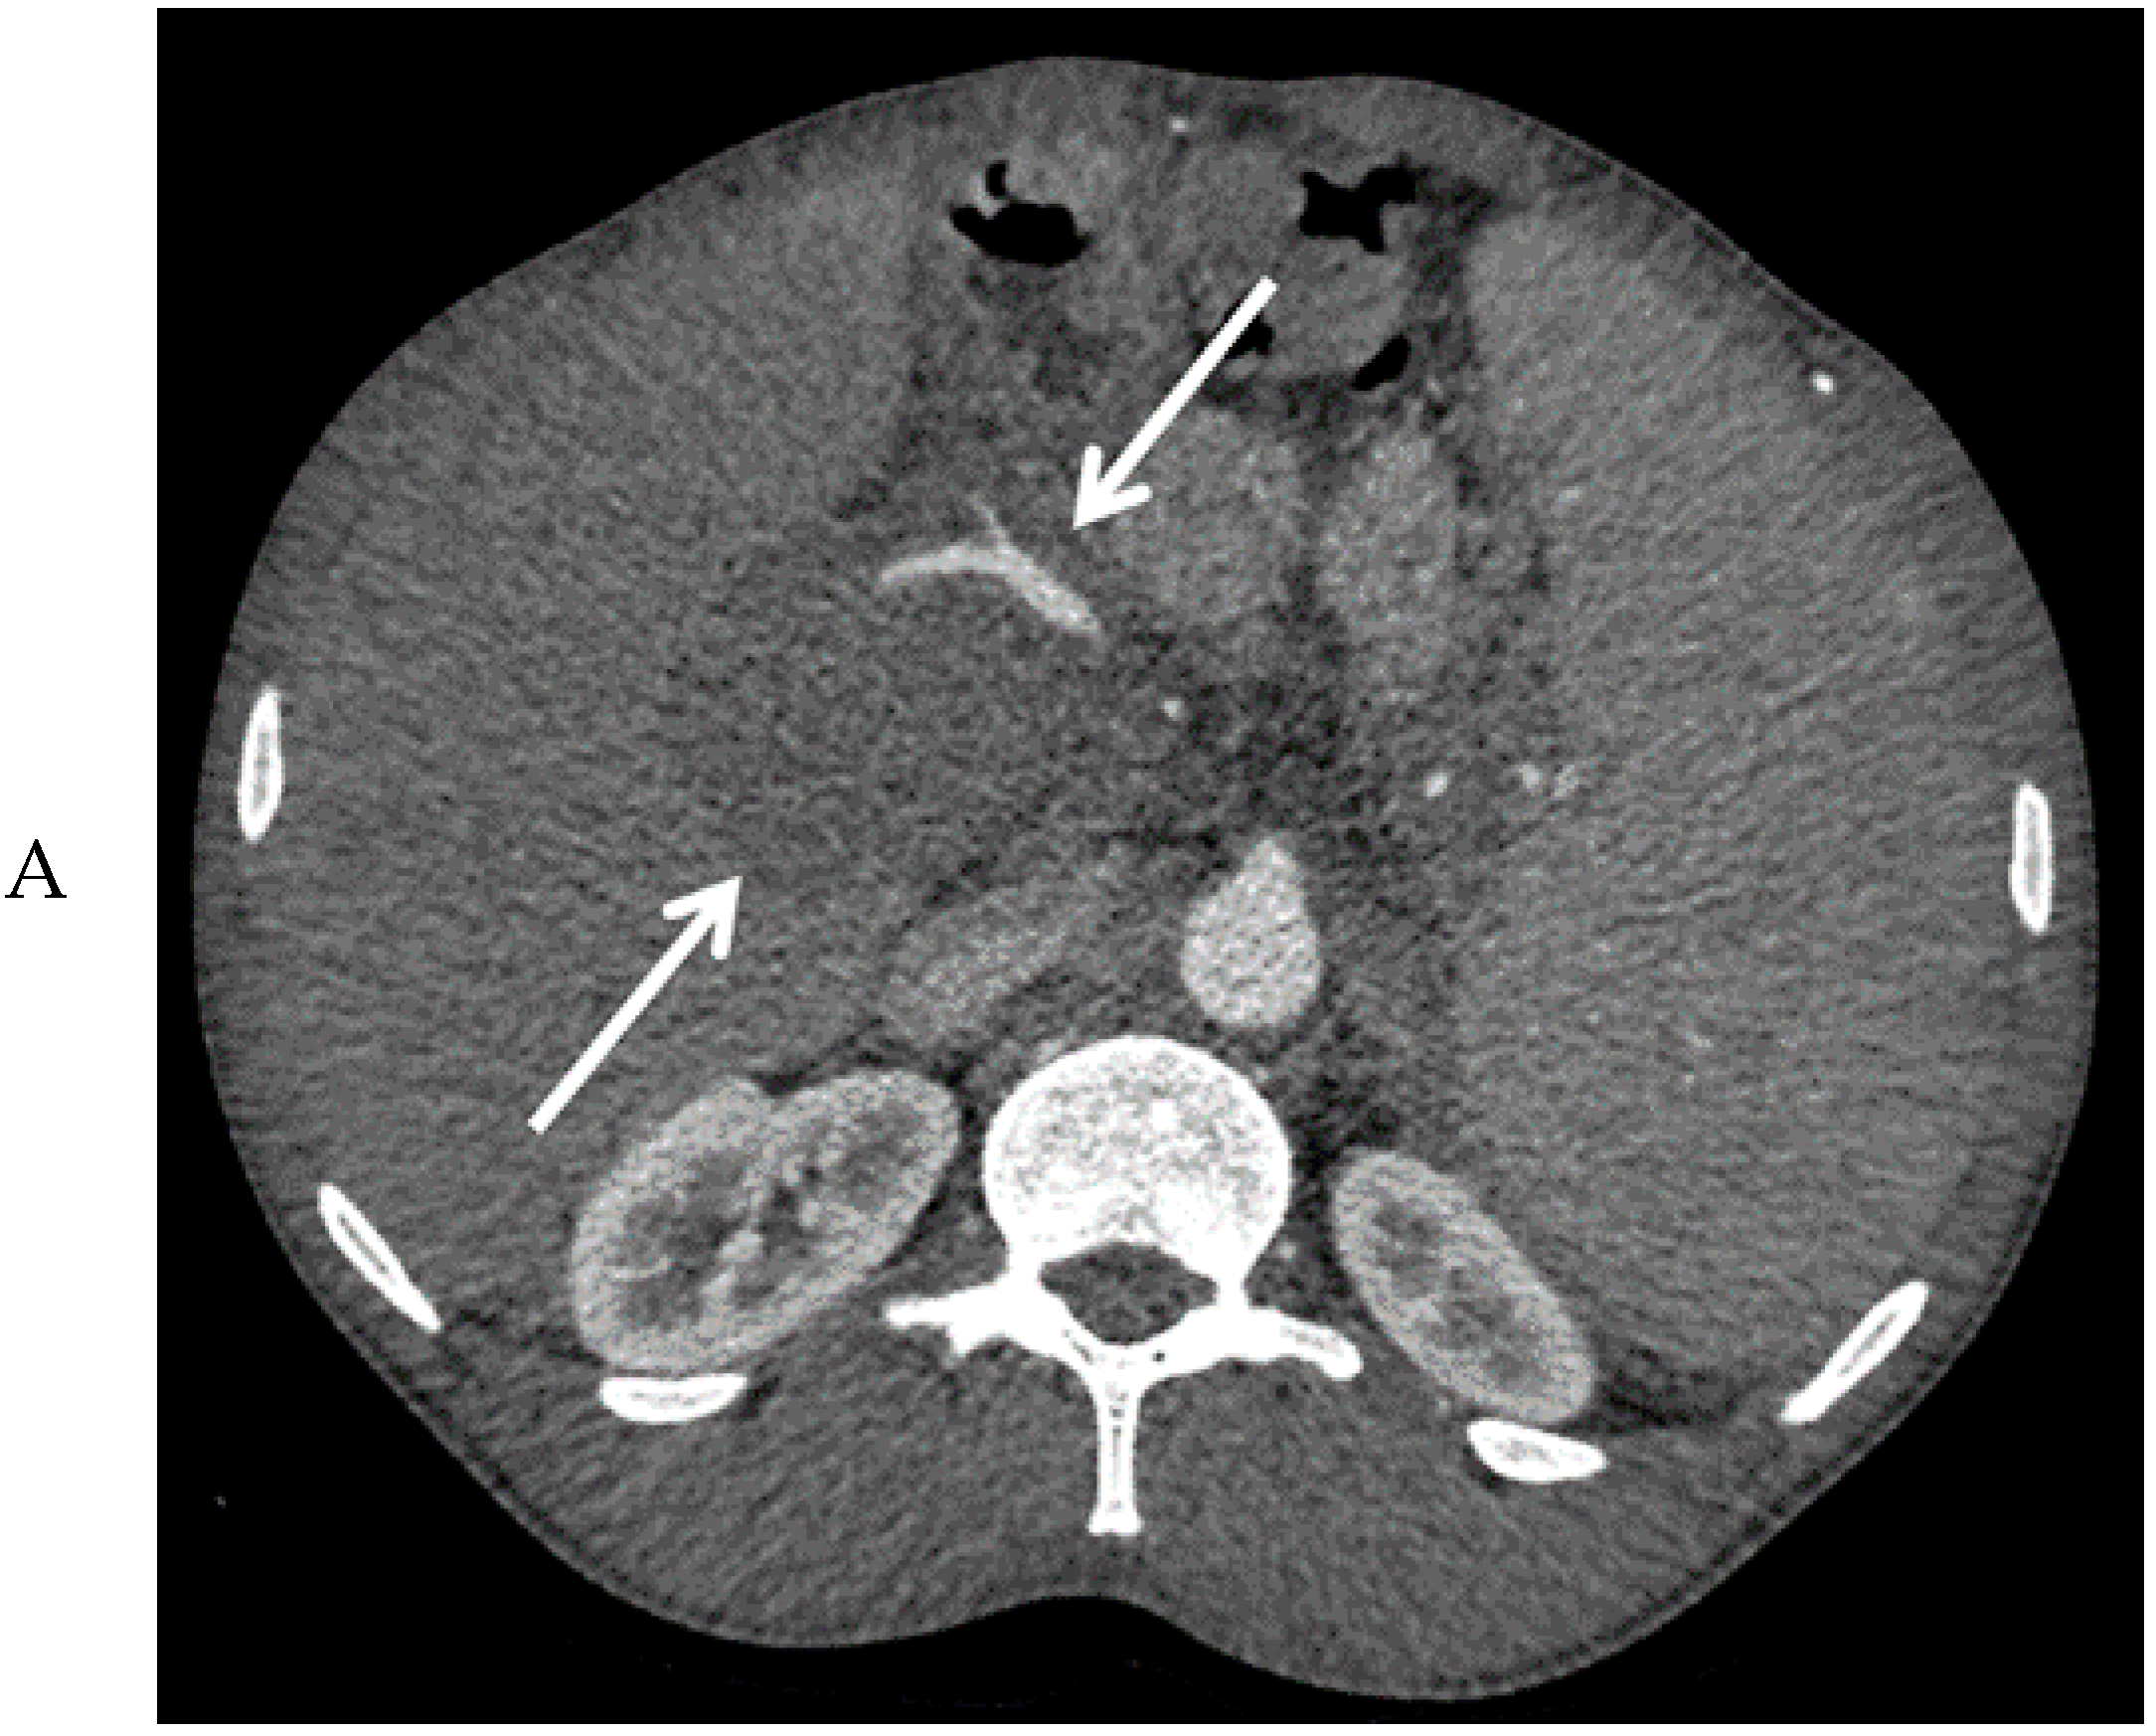

Abdominal ultrasound showed a large mass between the liver hilus and the pancreatic head (Figure 1), an enlarged spleen, and extensive collateral vessel formation. Contrast-enhanced computed tomography (CT) confirmed the presence of this mass with encasement of the hepatic arteries and common bile duct, dilation of the intrahepatic bile ducts, and portal vein thrombosis (Figure 2A,B). Due to the vascular encasement, the mass was deemed irresectable. An esophago-gastroduodenoscopy showed large esophageal varices. Elastography (FibroScan) showed only moderate (F2) liver fibrosis.

Figure 2. Computed tomography images of the mass in the upper abdomen (arrows) in the arterial (A) and portal venous phase (B).